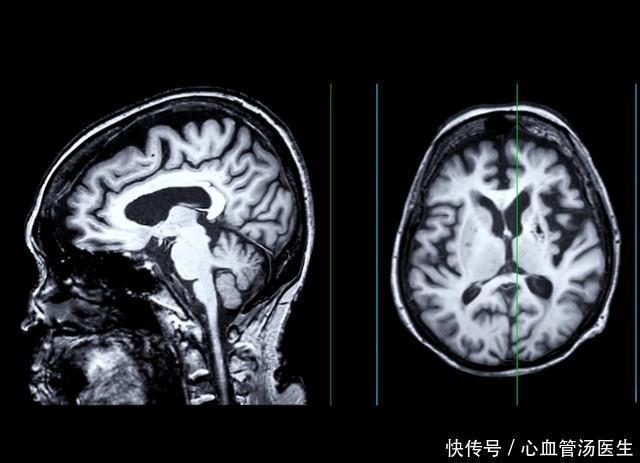

第七是头颅CT。对于高血压、糖尿病以及中老年人,头颅CT经常见到腔隙性脑梗塞,这说明脑部血管出现硬化,小血管局部堵塞,要注意管理好血压血糖血脂等,不要紧张,更不是住院治疗的指征。